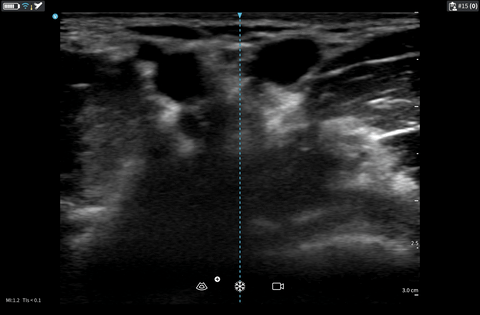

- Patency: Check whether a thrombus is present in the vein lumen. An uncompressible vein with echogenic thrombus is not suitable for cannulation. A patent compressible vein is shown on the right side in the following clip.